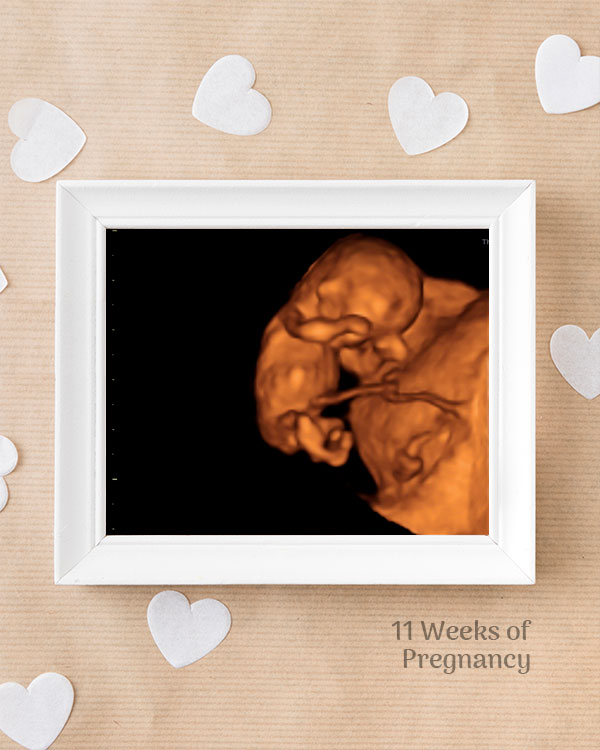

3D / 4D Baby Scan

Mediserv Diagnostics pioneered 4D scanning in the Malabar region. These advanced scans provide realistic images of the baby, allowing detailed evaluation of fetal structures and movements while creating a meaningful bonding experience for parents.